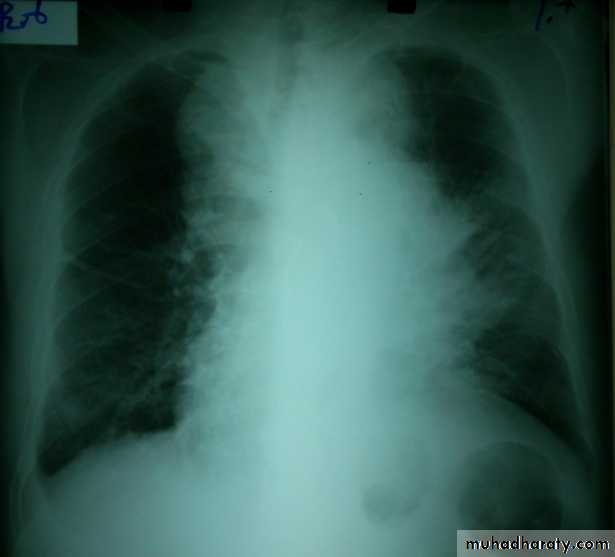

Chest radiography shows multiple pulmonary nodules of varying sizes consistent with metastatic cancer.

Chest CT scan shows multiple round nodules and masses of varying sizes in both lungs, consistent with metastases. There are also small bilateral pleural effusions.

Multiple and bilateral secondaries